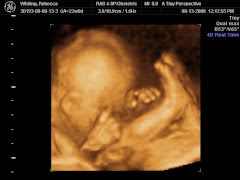

mark!! Becca proclaimed us to be finally readyfor the delivery of our little baby girl. This past week we received the dresser and the changing table at the house and I dutifully put them together. No cursing on my part either!! I do have to say they look great and Becca wasted no time in stuffing them with clothes. She set up a plan to keep all the clothes in order, but we will see how long that lasts, especially when it is the middle of the night and she needs a changing.

Her belly button reminds me of a turkey baster with how far it is poking out, which must mean that Baby Girl is almost done cooking :):) Last night we went on a haunted hayride, and for the record, I was against it!! She was adamant, though, and so we went. I guess my "Bouncer" abilities don't take effect until AFTER the baby arrives. Becca got her baby diaper bag the other day and I am waiting for my quinteesential Ironman diaper bag. (As an aside, the word "diaper" is kinda weird when you think about it. I mean, it isn't spelled the way you would think it should be given the spelling of the word. Just for giggles, I may add in the extra syllable and go for "dy-uh-per"). Things are well here and we are both TRE-mendously excited about the upcoming arrival of baby girl whiting!!